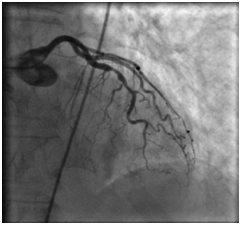

18.08.2011 выполнена селективная коронарная ангиография.

В процессе процедуры выявлено: ствол левой коронарной артерии обычно расположен. Передняя нисходящая артерия – в средней трети стеноз 80%.

Огибающая коронарная артерия без признаков стенозирующего атеросклероза.

Правая коронарная артерия – в средней трети стеноз 70%. Правый тип коронарного кровообращения.

Передняя межжелудочковая артерия

Правая коронарная артерия